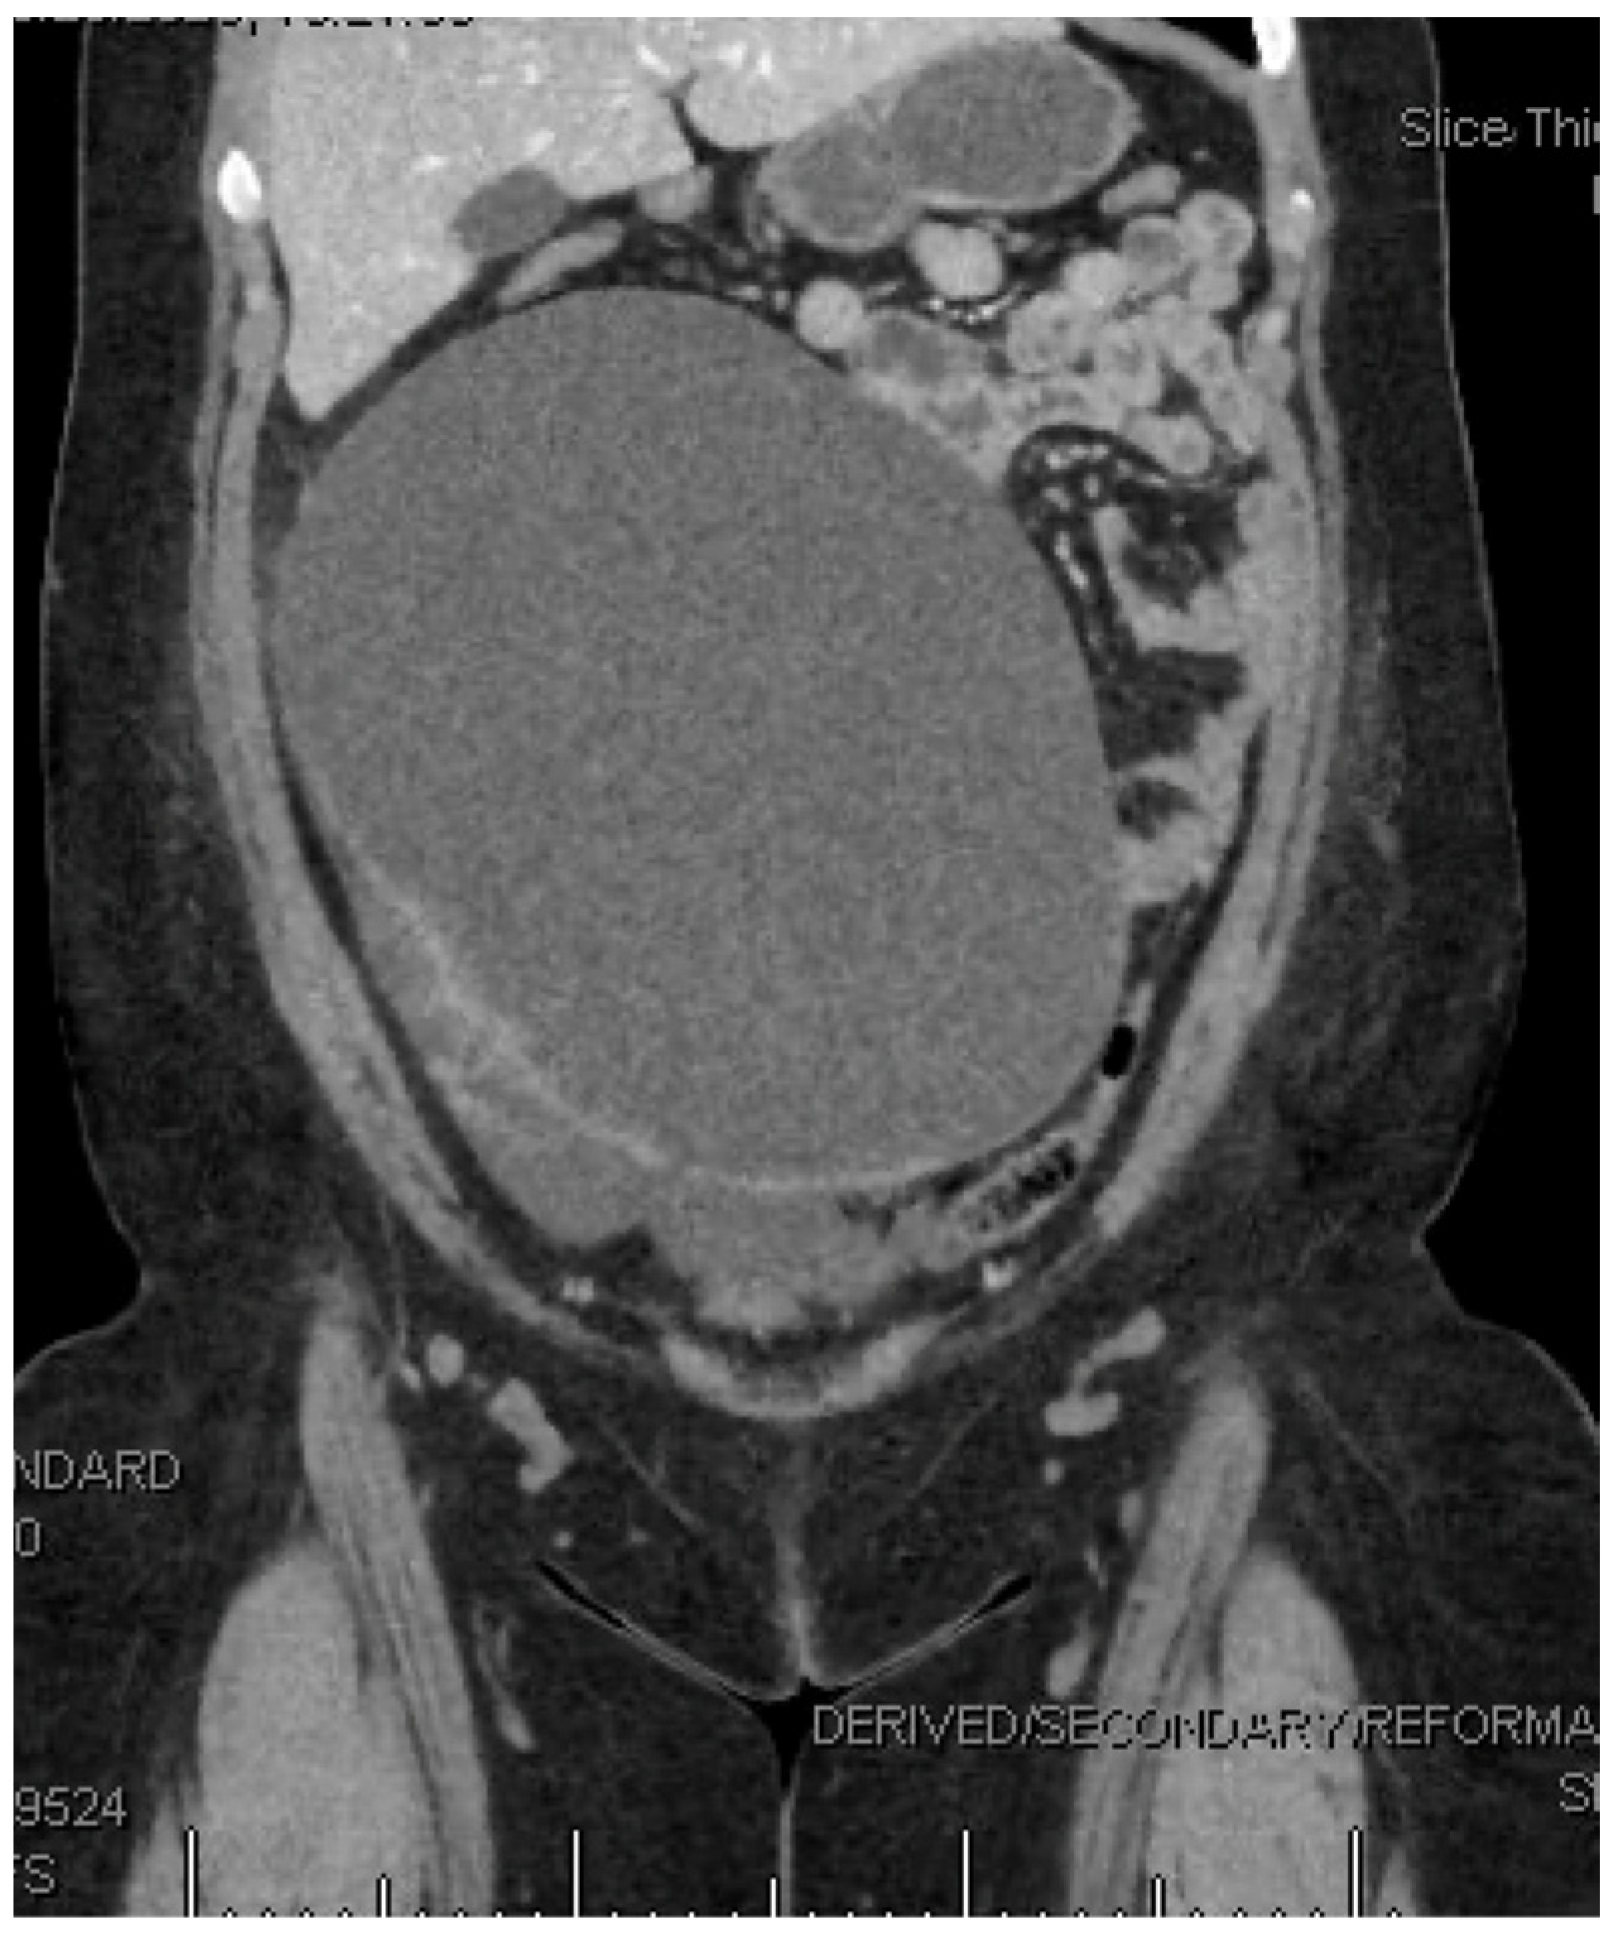

2. Detailed Case Description